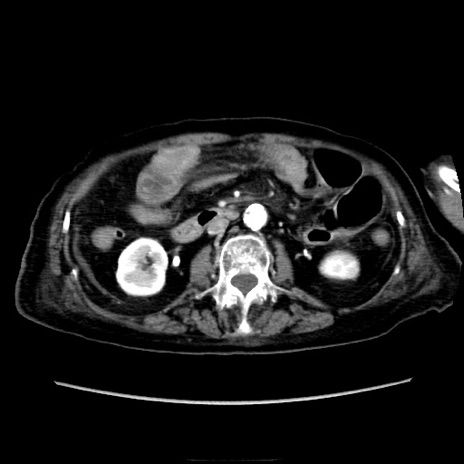

症例40(横断像)

【症例】90歳代女性

【主訴】腹痛・嘔吐

【現病歴】 食欲低下、嘔吐があり昨日他院受診。肺炎と診断され入院となる。入院後より腹部全体に圧痛あり。胃管留置され経過みていたが、症状持続するため、

当院転院となる。

【既往歴】胸椎圧迫骨折、胆石症

【身体所見】腹部:中央に激痛あり、圧痛あり、反跳痛不明

【データ】WBC 17100、CRP 18.82

横断像